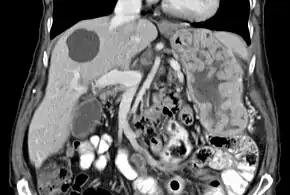

With Ménétrier disease, the stomach is characterized by large, tortuous gastric folds in the fundus and body, with the antrum generally spared, giving the mucosa a cobblestone or cerebriform (brain-like) appearance.[5] Histologically, the most characteristic feature is massive foveolar hyperplasia (hyperplasia of surface and glandular mucous cells).[3] The glands are elongated with a corkscrew-like appearance and cystic dilation is common. Inflammation is usually only modest, although some cases show marked intraepithelial lymphocytosis. Diffuse or patchy glandular atrophy, evident as hypoplasia of parietal and chief cells, is typical.[4]

The large folds of the stomach, as seen in Ménétrier disease, are easily detected by x-ray imaging following a barium meal or by endoscopic methods. Due to the thickened rugae folds, it is said to have a cerebriform (brain-like) appearance.[7][8] Endoscopy with deep mucosal biopsy (and cytology) is required to establish the diagnosis and exclude other entities that may present similarly. A non-diagnostic biopsy may lead to a surgically obtained full-thickness biopsy to exclude malignancy.[3] CMV and helicobacter pylori serology should be a part of the evaluation.